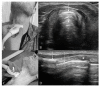

Airway management is a common and critical procedure in acute settings, such as the Emergency Department (ED) or Intensive Care Unit (ICU) of hospitals. Many of the traditional physical examination methods have limitations in airway assessment. Point-of-care ultrasound (POCUS) has emerged as a promising tool for airway management due to its familiarity, accessibility, safety, and non-invasive nature. It can assist physicians in identifying relevant anatomy of the upper airway with objective measurements of airway parameters, and it can guide airway interventions with dynamic real-time images. To date, ultrasound has been considered highly accurate for assessment of the difficult airway, confirmation of proper endotracheal intubation, prediction of post-extubation laryngeal edema, and preparation for cricothyrotomy by identifying the cricothyroid membrane. This review aims to provide a comprehensive overview of the key evidence on the use of ultrasound in airway management. Databases including PubMed and Embase were systematically searched. A search strategy using a combination of the term "ultrasound" combined with several search terms, i.e., "probe", "anatomy", "difficult airway", "endotracheal intubation", "laryngeal edema", and "cricothyrotomy" was performed. In conclusion, POCUS is a valuable tool with multiple applications ranging from pre- and post-intubation management. Clinicians should consider using POCUS in conjunction with traditional exam techniques to manage the airway more efficiently in the acute setting.